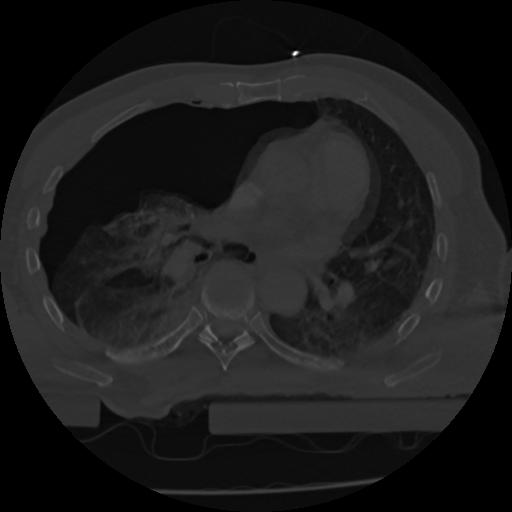

22 ANGIO,CE,Vol,0.5,ANGIO,,